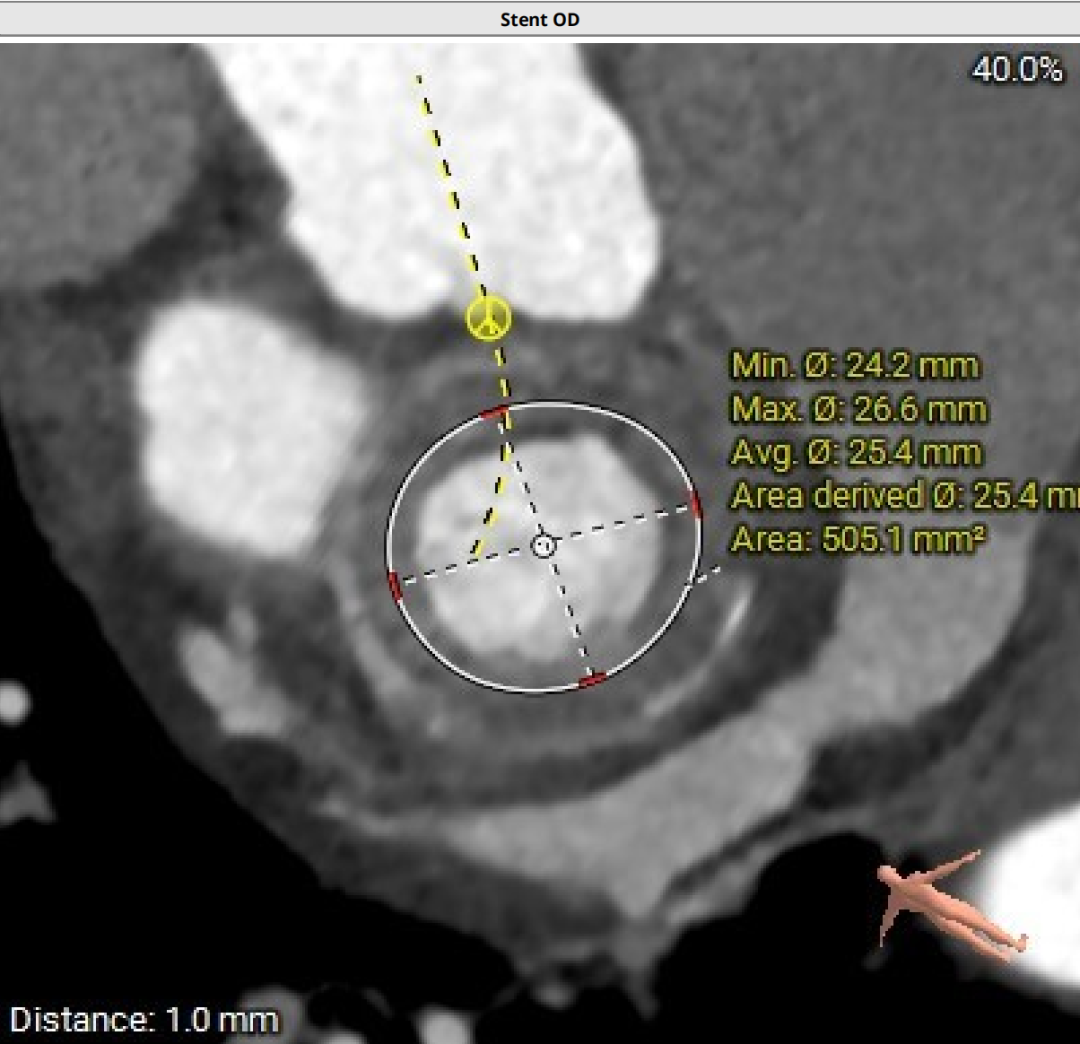

术前CT分析

二尖瓣生物瓣架内径23mm,外径25mm,根据瓣架形态,符合25#Mosaic瓣膜